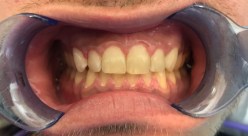

*Extraction & bone graft planned for #7 future implant